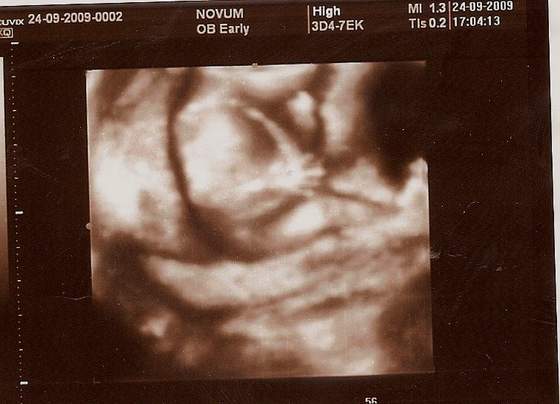

Buziaczek dla kruszynki albo kruszynkaa to mój kruszynek)) albo kruszynka :-):-):-)

a to mój kruszynek)) albo kruszynka :-):-):-)